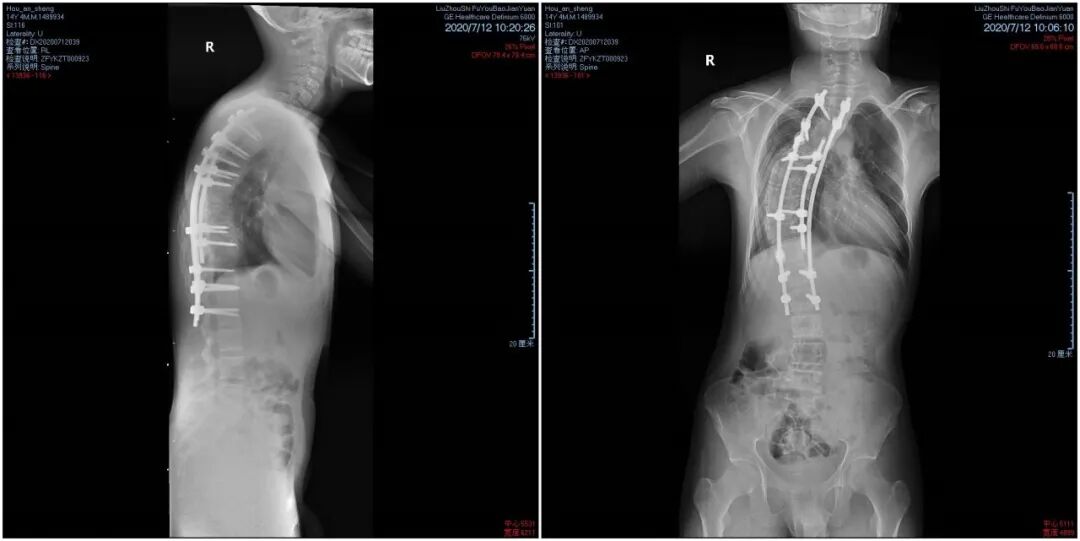

今年14岁的小胜来自三江县古宜镇的一个贫困家庭。因重度脊柱侧弯107度,他的背部严重畸变成S形,肺部被脊柱压迫,生命受到威胁。这个病,困扰了他整整三年。

术后,小胜“剃刀背”畸形得到改善,脊椎平衡得到纠正。如今脊柱侧弯程度不到50度,身型从外观看基本恢复了正常,对生活基本不会造成太大影响。